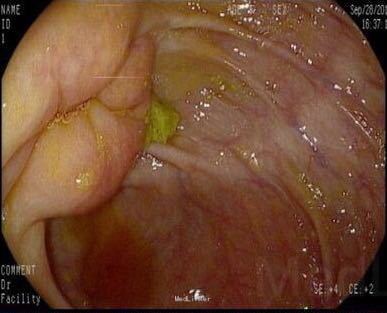

入院后完善相关检查 血常规:白细胞计数 13.84 ↑ 4~10 10^9/L。尿液分析及尿沉渣:白细胞 +- 阴性隐血 +- 阴性蛋白质 1+ 阴性糖 4+ 阴性,酮体 2+ 阴性。 生化全套2:白蛋白 32.9 ↓ 35~55 g/L球蛋白 39.9 ↑ 20~35 g/L白球比值 0.82 ↓ 1~2.5葡萄糖 20.85 ↑ 3.82~6.1 mmol。血脂肪酶及淀粉酶正常。红细胞沉降率 53 0~20 mm/h。糖化血红蛋白 11.7 ↑ <6 % 肿瘤全套2:癌胚抗原 405.13 ↑ 0~5 ng/ml,糖类抗原19-9 >1200.00 ↑ 0~37 U/mL。 头颅CT平扫未见明显异常。 胸部+上腹部CT提示:1.胃积气扩张,余上腹部CT平扫未见明显异常。2.肺气肿,支气管炎肺部表现;3.双肺间质性肺炎;4.主动脉硬化;5.主动脉窦致密影,考虑瓣膜钙化。 胰腺增强:1 胰腺CT增强未见明显异常。2 右肾小囊肿。 肠镜检查:大肠黑变病。胃镜检查:浅表性胃炎(2级)。 复查癌胚抗原 383.42 ↑ 0~5 ng/ml糖类抗原19-9 >1200.00 ↑ 0~37 U/mL,仍旧显著升高,为进一步排除肿瘤行病变,遂行盆腔磁共振检查:1.盆腔右侧占位,肿瘤性病变不除外,建议增强扫描。2.右侧附件区结节影,建议增强扫描。3.子宫肌层信号欠均匀,不除外腺肌病可能。4.盆腔少许积液。

请妇科会诊,该科医师行妇检未见明显包块,且CA125正常,建议行小肠检查,同时行彩超探查了解包块来源,妇科彩超:子宫较小,宫体后壁肌壁间肌瘤(稍凸向宫腔),右侧附件区实质性包块,考虑为右侧卵巢肿瘤,左侧附件区未见明显异常显示,盆腔未见明显积液。 请妇科商议并于患者沟通后于2015.10.08转入妇科,转科行积极完善术前准备,于10.16行剖腹探查术。术中见:子宫稍大,质硬,后壁与直肠致密粘连,左侧卵巢大小正常,右侧卵巢增大直径约4cm,双侧附件与子宫后壁及盆壁致密粘连,分离盆腔粘连后可见巧克力样液体,阑尾可见约9*5*4cm肿瘤,包膜完整,与周围组织无粘连。请胃肠外科主任上台会诊,行阑尾切除术,术中快速病理切片检查示:(阑尾)腺上皮高级别上皮内瘤变(腺上皮中-重度异型增生),确诊待常规。再次向家属交代病情,将快切结果告知患者家属,患者家属了解病情,要求切除右半结肠,切除全子宫及双侧附件,最终行:全麻插管下行右半结肠根治性切除+肠粘连松解+腹式全子宫切除+双侧卵巢输卵管切除术。术后病检提示:(阑尾)中分化腺癌,癌浸润达肌层。阑尾手术切缘未见癌组织。免疫组化:CK19(+),Ki-67 LI约60%。子宫附件及右半结肠:1.送检肠管粘膜组织呈慢性炎,粘膜下水肿,纤维脂肪组织增生,血管扩张、充血。肠周触及淋巴结13枚呈反应性增生。 2.子宫腺肌症,囊性萎缩性子宫内膜组织,慢性子宫颈炎伴鳞状上皮化生。 3.(双侧)卵巢白体形成,(右侧)符合子宫内膜异位囊肿;(双侧)输卵管组织呈慢性炎,(右侧)伴系膜囊肿。